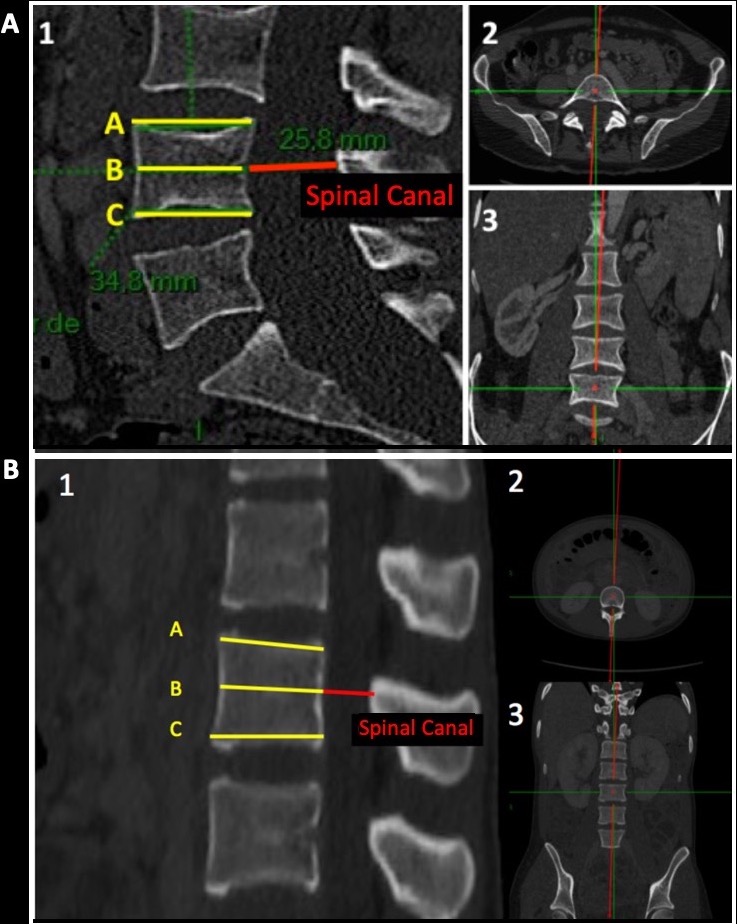

-the Antero-Posterior Diameter of the Spinal Canal (APDSC), taken perpendicular to the dural sac axis and the vertebra with zoom and alignment permitted by a multiplan reconstruction mode (MPR) (in Red on Pannels A and B).

-the Scalloping, determined using the measures of the superior (A) and inferior (B) vertebral plateau and the antero-posterior diameter at the center of the vertebra core (C), with the following formula: (A+B)/2-C. Each measurement is performed on the sagittal plan, zooming on each vertebra, and alignment in MPR mode at the center of the vertebra and perpendicular to its axis (Pannels A and B).